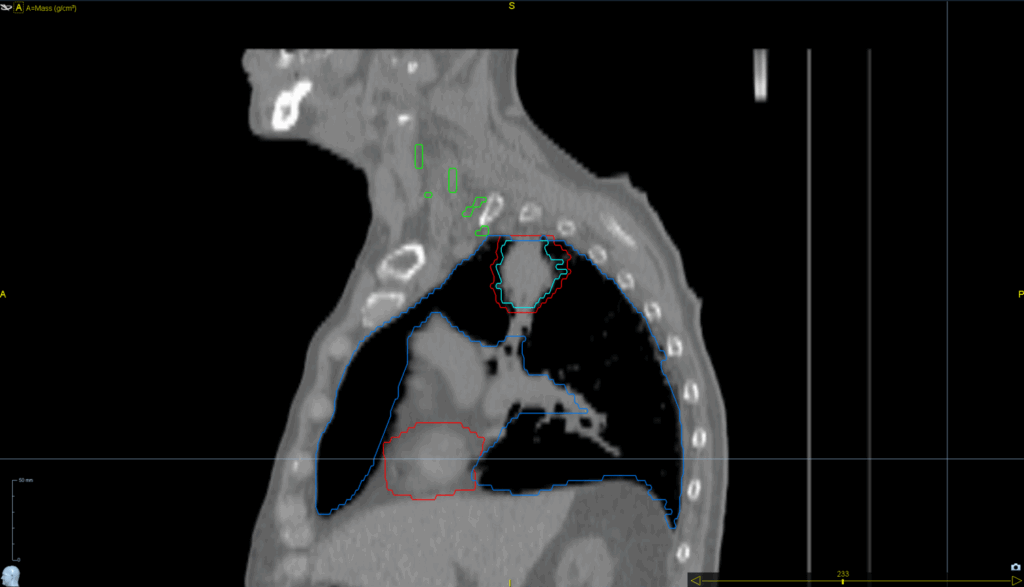

Planning CT Images